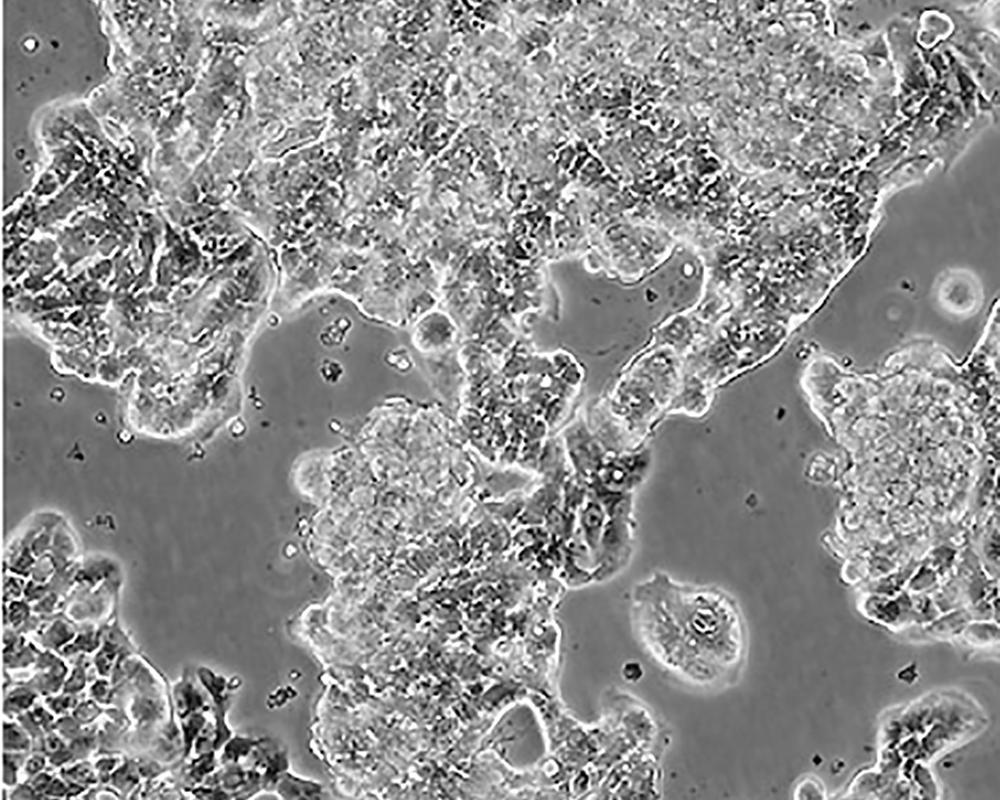

形態特征 epithelial

細胞描述 該細胞產生高水平的黏液素MUC-1 mRNA,低水平的MUC-2 mRNA,但不表達MUC-3基因;表達雌激素受體。